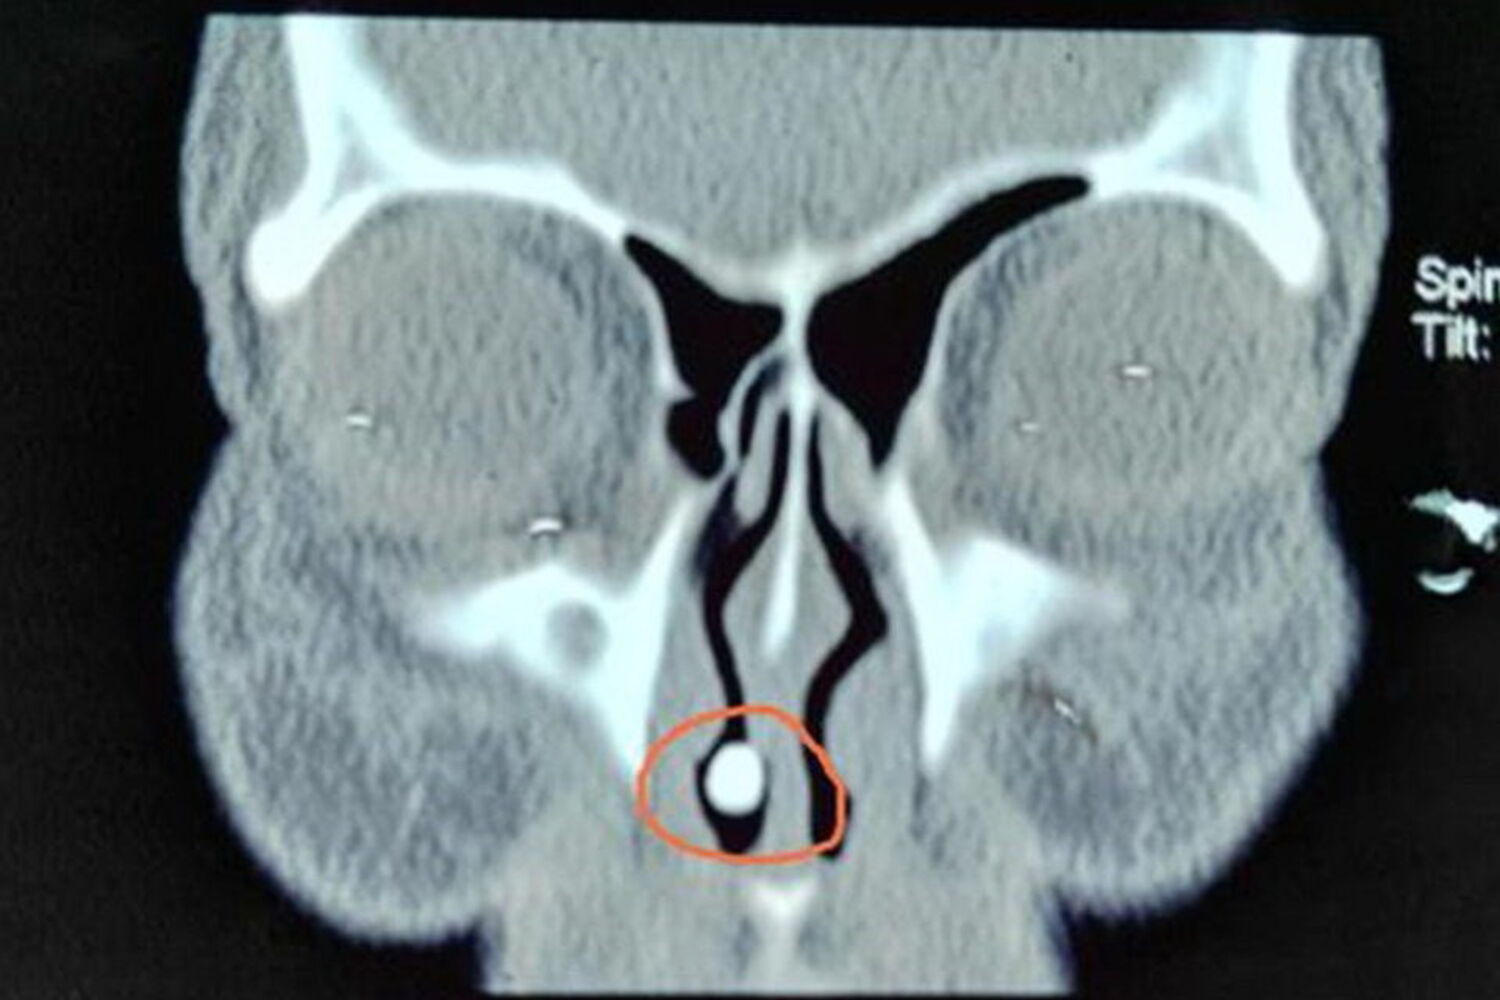

Os médicos estranharam as hemorragias constantes e que duravam há cerca de 50 anos e resolveram fazer a tomografia. O exame revelou uma "massa de alta densidade na cavidade nasal direita".

"Pensamos que fosse um objeto que ali tinha sido introduzido, ou uma pedra que ela em criança tivesse posto ali e ficado alojada", contam os médicos. Mas a cirurgia revelou um achado bem mais insólito: tratava-se de um dente que tinha nascido no nariz da paciente. Estava completo, tinha coroa e raiz.